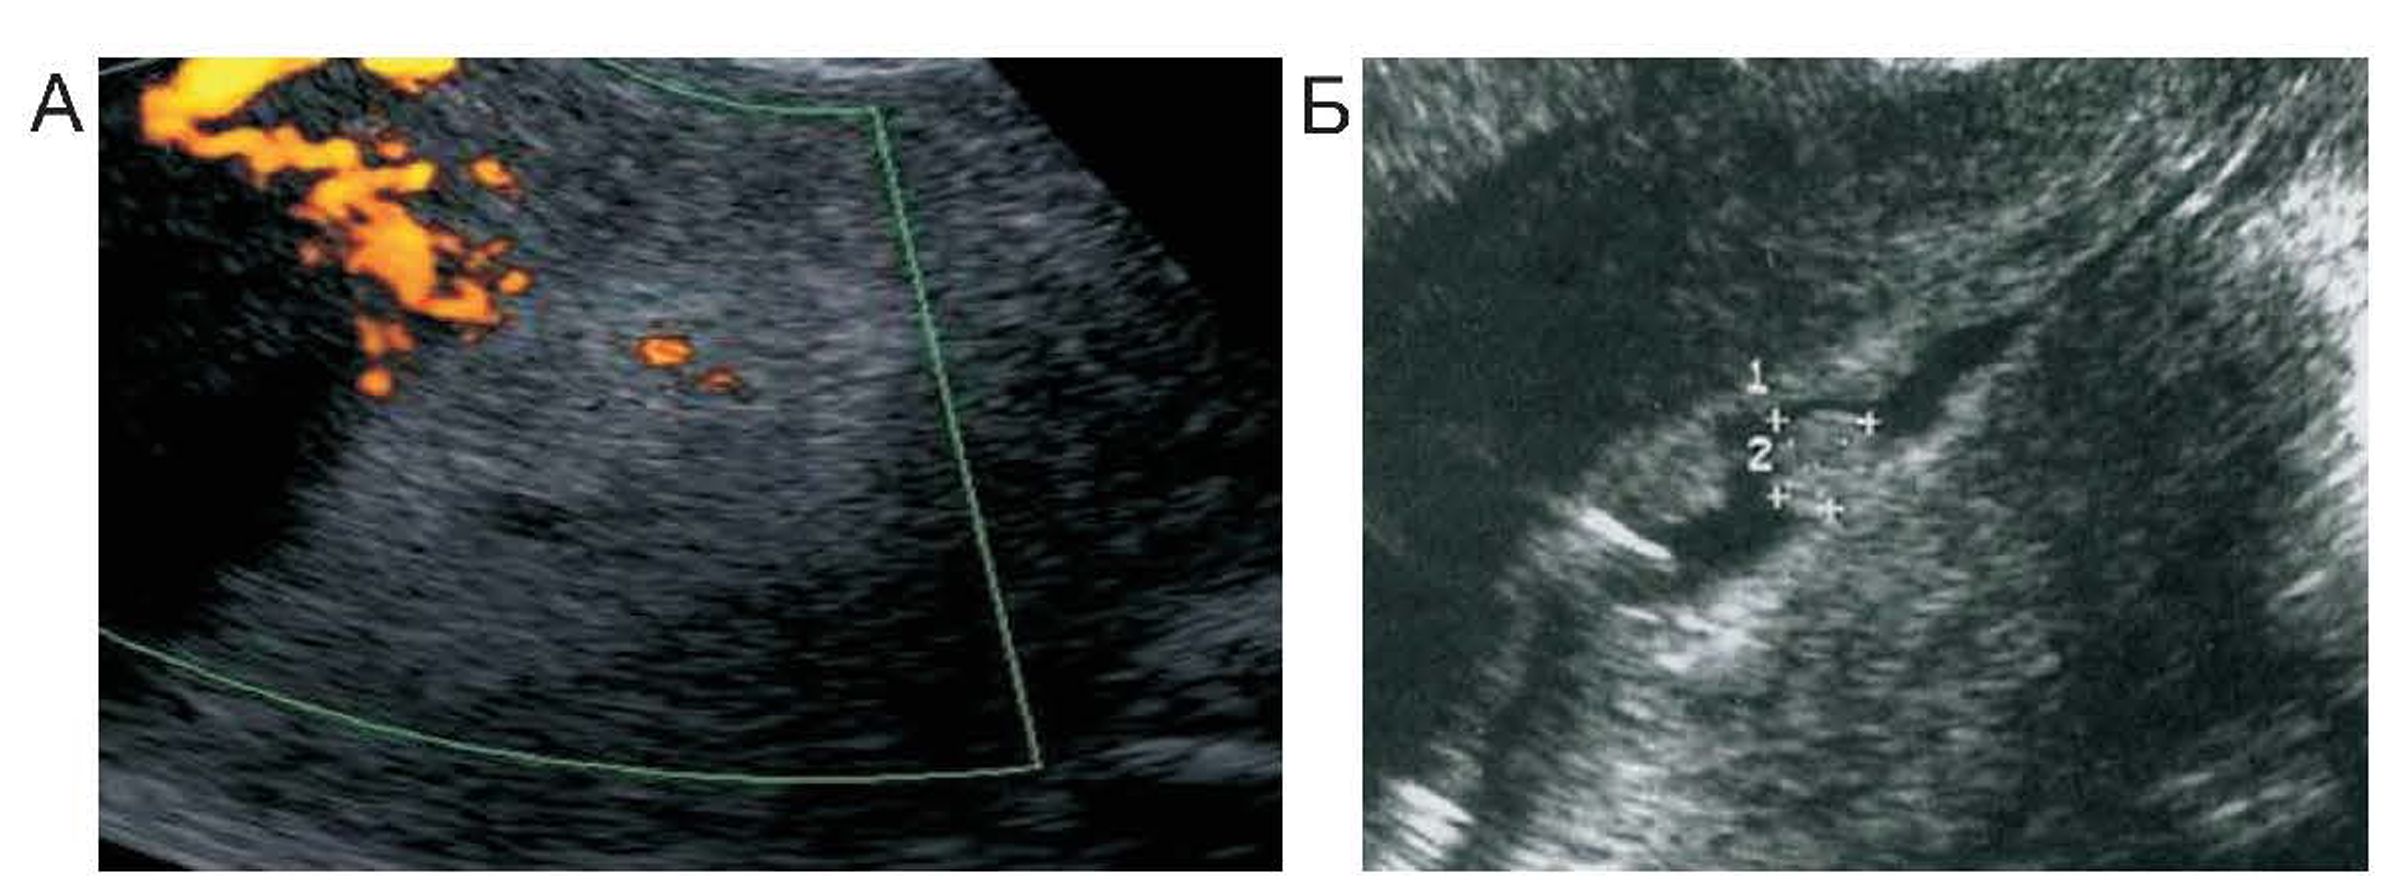

Таким образом, мы еще раз акцентируем внимание на том, что ультразвуковая картина изменений эпителия матки при длительном приеме тамоксифена имеет ряд особенностей: гетерогенность структуры; множественные анэхогенные кистозные включения разного диаметра; срединные маточные структуры утолщены в сравнении с нормой в постменопаузе. При этом толщина эндометрия может иметь размеры атрофии (1-2 мм) с полиповидными включениями, или значительно увеличиваться и иметь неоднородные кистозные лакуны (рис. 2).

Рис. 2. Ультразвуковая картина изменений эпителия матки при длительно/и приеме тамоксифена

При истинной гиперплазии эндометрия, также, как и при раке, картина эндометрия имела несколько эхографических картин: диффузное утолщение эндометрия с диффузными локусами кровотока, при допплерометрии индекс резистентности варьировал от 0,43 до 0,6; локальное неравномерное утолщение эндометрия в области дна или трубного угла с участками кровотока внутри гипоэхогенной структуры; гипоэхогенные полиповидные включения, деформирующие контур полости матки с единичными участками кровотока (рис. 3).

Рис. 3. А. — гиперплазия эндометрия, Б. — полип эндометрия у пациенток РМЖ, принимающих тамоксифен более 6 мес.